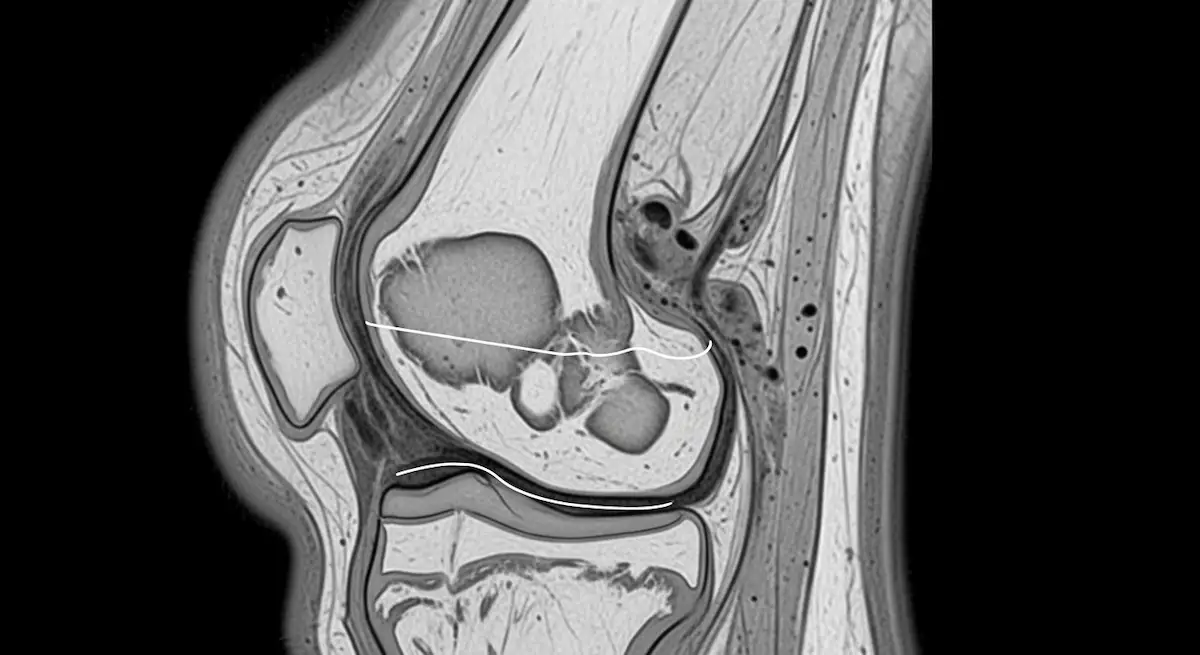

Lesões e Doenças do Joelho  Síndrome de Hoffa: o que é, sintomas e tratamentoA síndrome de Hoffa é uma inflamação do coxim gorduroso infra-patelar que causa dor na parte anterior do joelho. O… Leia mais »